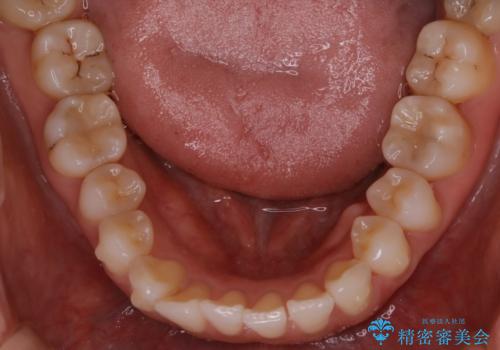

【非抜歯】前歯のガタつき マウスピースの部分矯正

- 上下の前歯の細かいガタつきの治療をご希望されて来院されました。

奥歯部分にはガタつきや噛み合わせの問題などがほとんど見られず、前歯のガタつきも軽度だったため、インビザライン ライト パッケージでの部分矯正を行うこととなりました。

今回のケースでは奥歯の噛み合わせに問題がほぼみられなかったため、前歯の位置のみに焦点を当て部分矯正を行いました。

適応されるケースが限られるものの、適応であった場合の治療期間は全体矯正と比べると格段に短くなり、費用も抑えられます。